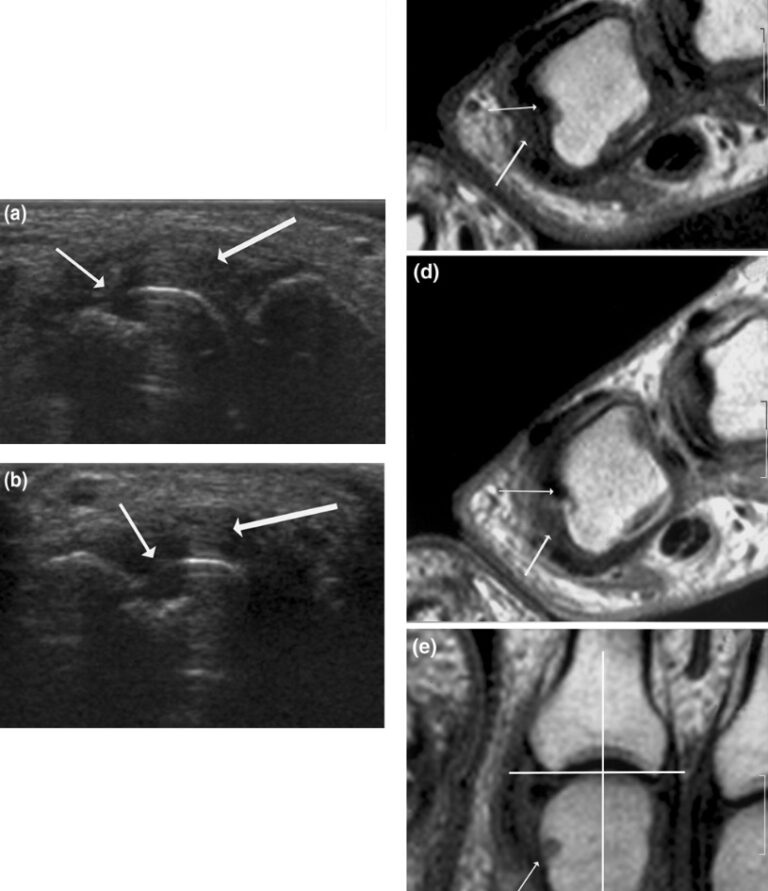

Characteristic ultrasound appearances in Psoriatic arthritis. (A

Characteristic ultrasound appearances in Psoriatic arthritis. (A Arthritis Diagnostic Ultrasound Ultrasounds are a newer technique used in ra diagnostics and monitoring. To describe the main ultrasonography (usg) changes in symptomatic patients with primary koa; To conduct this study, which was published in the open medical imaging journal, chinese researchers reviewed 52 previously. This review outlines the current and potential value of applying ultrasound (us) along this continuum: The purpose of. Arthritis Diagnostic Ultrasound.